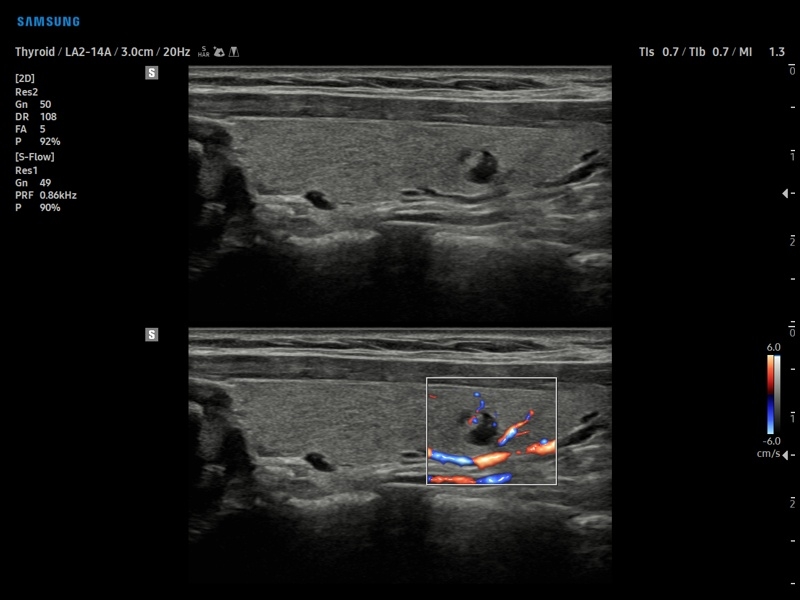

• S-Detect для исследования молочной железы и щитовидной железы

• МодульS-Detect Thyroid- программа автоматического обнаружения образований и анализа щитовидной железы, измерение и классификация по системе системе TI-RADS.

• Модуль S-Detect Thyroid - программа автоматического обнаружения образований и анализа щитовидной железы, измерение и классификация по системе системе TI-RADS.

• Модуль Elastoscan - программы эластографии для исследований щитовидной железы, молочной железы у женщин и предстательной железы у мужчин.

• Модуль S-Shearwave imaging – программа цветовой сдвиговой эластографии позволяющая автоматически определять индекс жесткости различных участков исследуемого объекта в кПа или м/с, получая при это еще и индекс достоверности данных RMI.